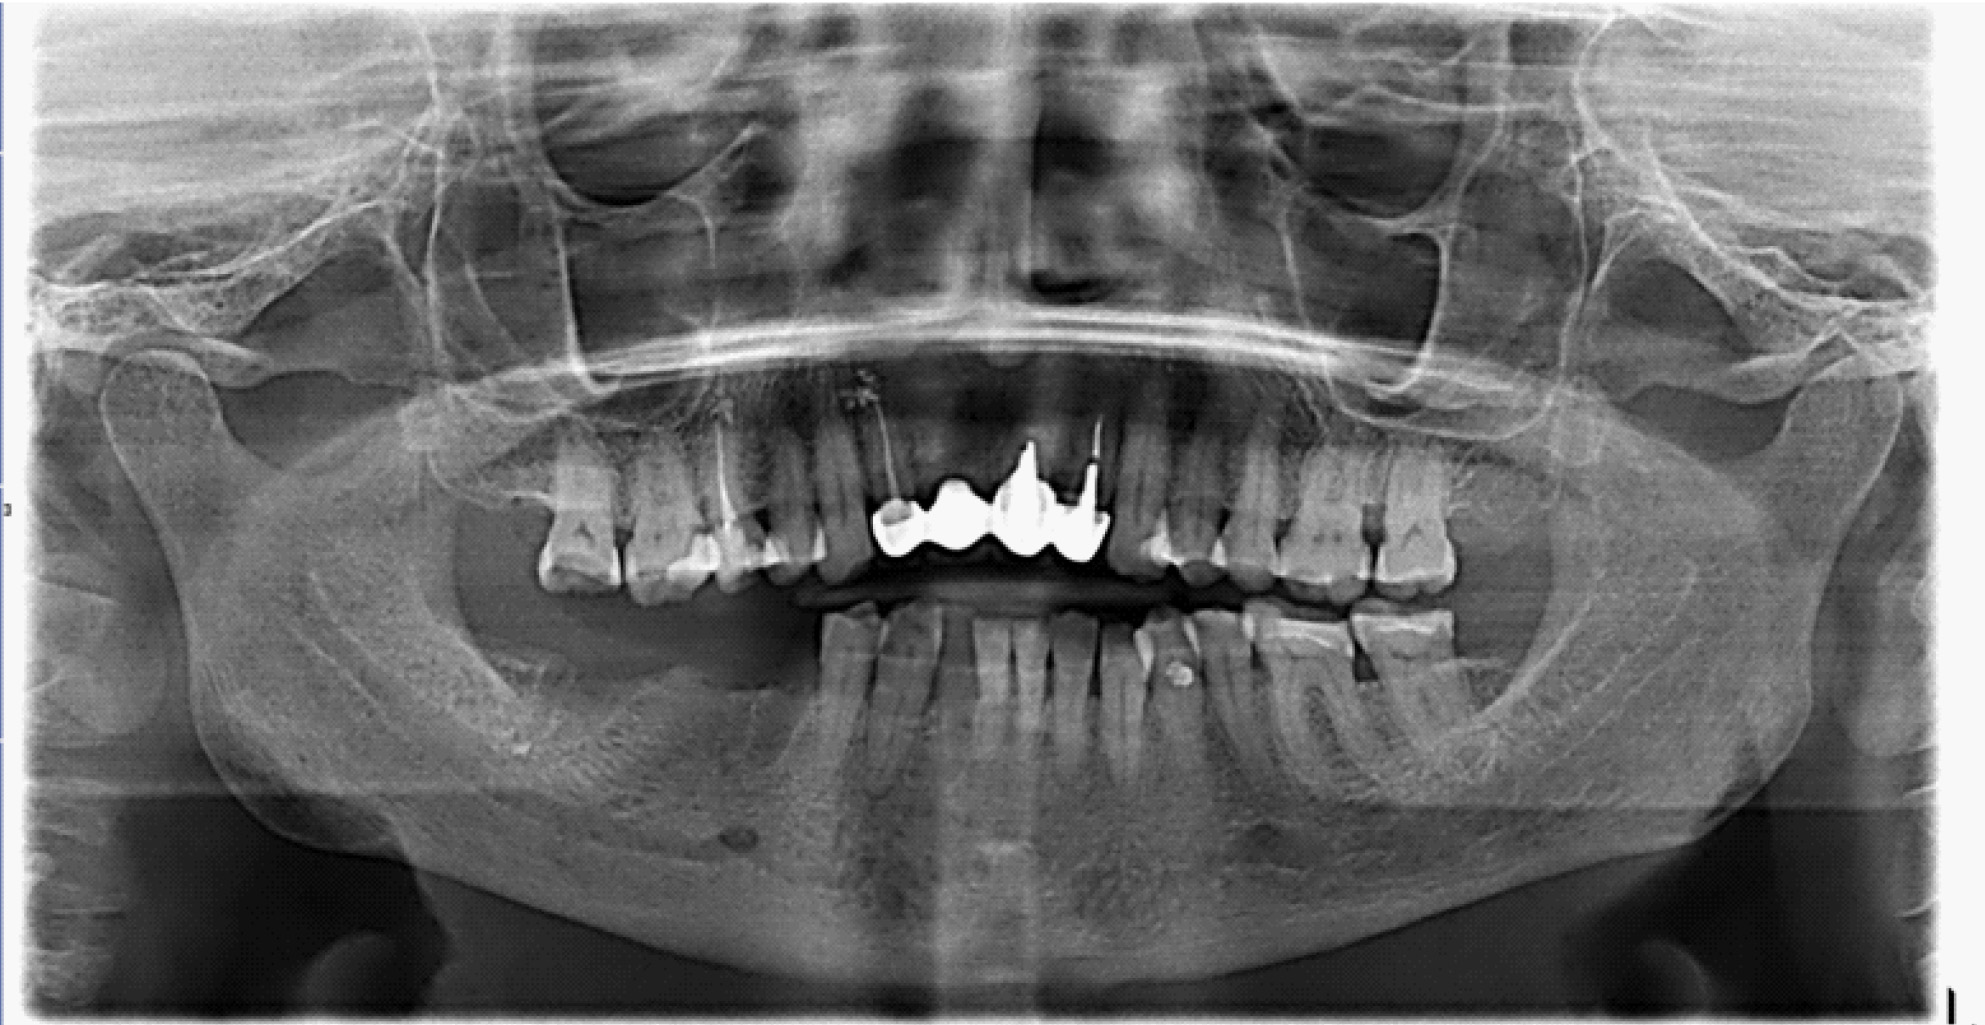

За период лечения пациентки Б. было выполнено хирургическое лечение в следующем объеме: кюретаж лунок удаленных зубов, частичная секвестрэктомия, резекция альвеолярной части нижней челюсти справа, вскрытие и дренирование гнойных очагов в стадии обострения патологического процесса. Отмечалось улучшение клинической и рентгенологической картины в полости рта (рис. 5, 6).

Рис. 5. Клинические проявления бисфосфонатного остеонекроза нижней челюсти справа у пациентки Б. в 2024 году

Рис. 6. Ортопантомограмма на этапе лечения остеонекроза нижней челюсти справа у пациентки Б. в 2024 г.